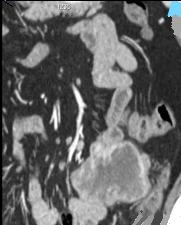

| Tumeur de GIST a distal de

ileon , image homogene a hypo-dense , poly lobulaire

et extraluminale . Image TDM en coupe coronal . |